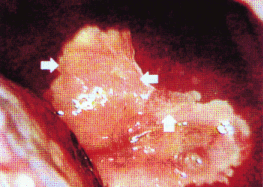

Fig. 14-4. Teste de Schiller positivo.